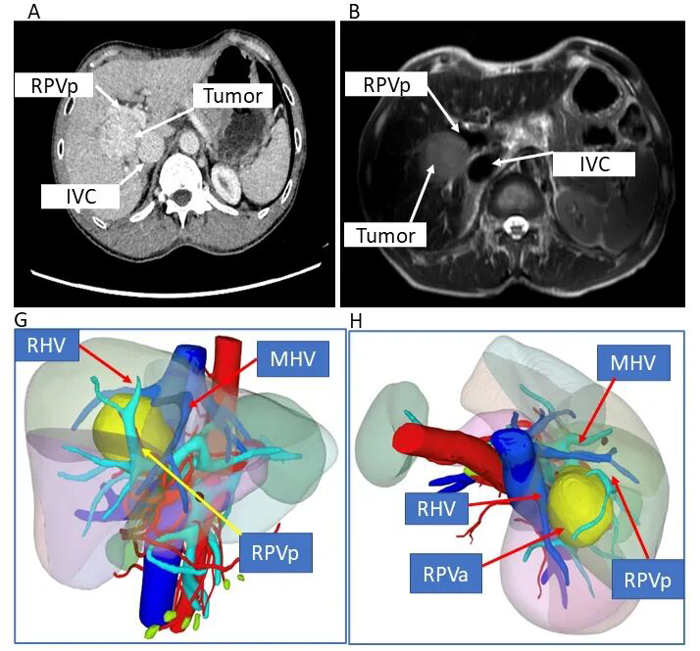

▲李大爷CT显示,肿瘤位于肝脏所有大血管围成的“危险三角区域”。

2023年,56岁的李大爷(化名)因肝纤维化合并肝癌入院。肿瘤侵犯“第二肝门”,即肝脏血液回流进入心脏的核心危险区域,常规切除会导致肿瘤残留和残余肝脏体积不足;而异体肝移植则面临费用高昂、供体匹配困难、免疫排斥等问题。

团队创新构建了“病肝在体劈离后取出——门体静脉转流——体外低温灌注下精准肿瘤切除——无瘤健康肝组织原位回植”的自主技术体系,实现了“术中少出血、肿瘤零残留、残肝够功能”的目标。术后,李大爷恢复良好,如今已能正常生活。

在临床实践的同时,团队高度重视学术研究。针对肝脏“雷区”肿瘤的诊治经验与技术创新成果,已发表于国际知名肿瘤学期刊《Frontiers in Oncology》,向全球同行分享我院的诊疗方案,标志着该项技术已达到国际先进水平。